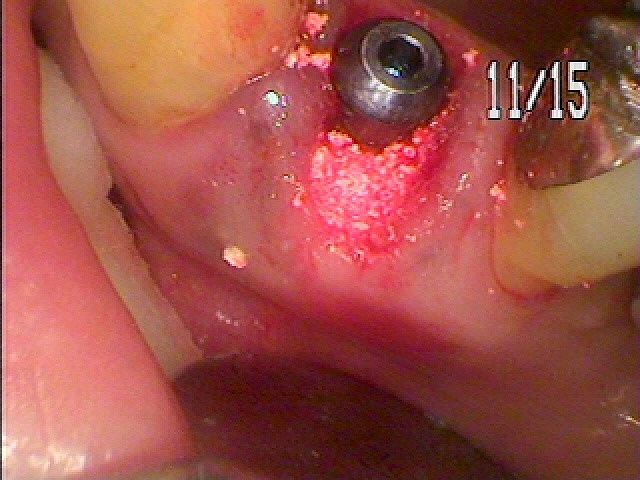

骨補填材を転入していきました